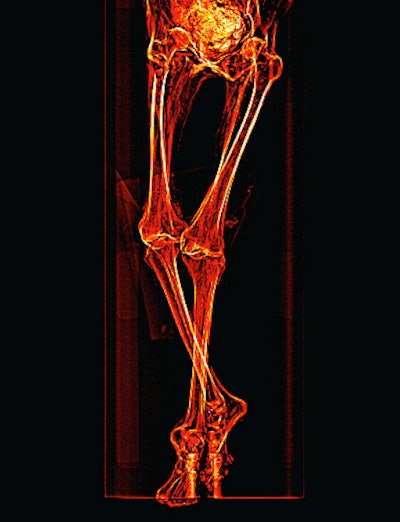

Saleem obtained maximum length measurements of the major long bones. The right femur measured 402 mm, left femur 401 mm, right tibia 338 mm, left tibia 338 mm, right fibula 338 mm, and left fibula 339 mm. Because of the oblique posture of the mummy, it was impossible to obtain a vertex-to-heel measurement. The stature was estimated to be about 151 cm ± 2.5 cm based from the femur length using regression equation derived for ancient female Egyptians.

She noted that definite atherosclerotic changes are visible as high-density areas of calcification within the walls of identifiable arteries: right and left carotid bulbs, right and left coronary arteries, abdominal aorta, superior mesenteric artery, coeliac artery, bilateral iliac, femoral and peripheral leg arteries. Also evident was mild lateral curvature of the dorsal spine with its convexity to the left (scoliosis); no structural abnormalities of the spine or anomalous vertebrae could be seen.